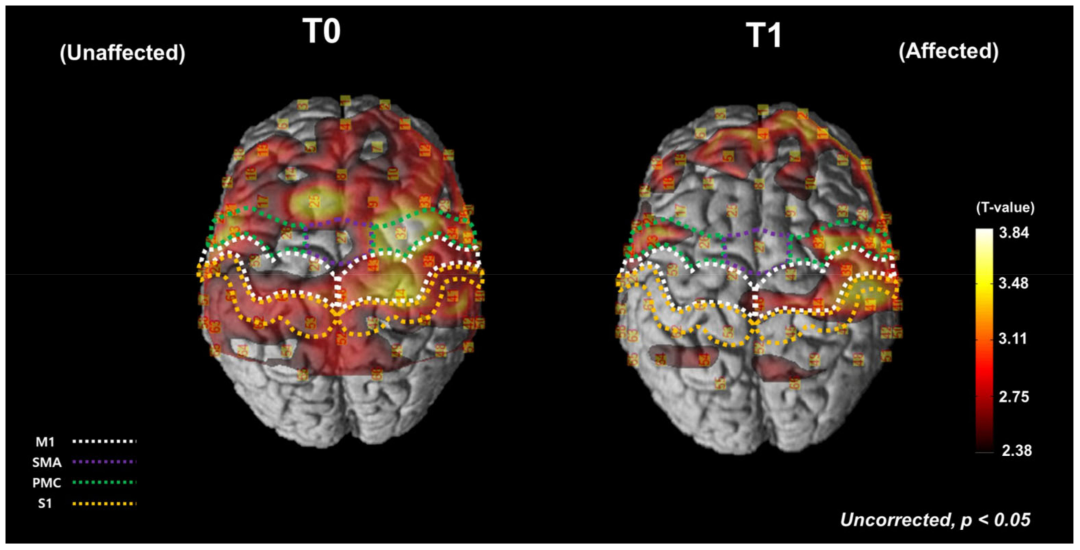

fNIRS結(jié)果(圖3):

組水平(SPM統(tǒng)計(jì)參數(shù)映射)分析:干預(yù)前(T0),患者執(zhí)行FTT時(shí)雙側(cè)半球均被激活。干預(yù)后(T1),激活主要集中于患側(cè)半球,整體激活范圍減小。這表明半球間平衡得到改善。

圖3 fNIRS-SPM 皮層激活圖